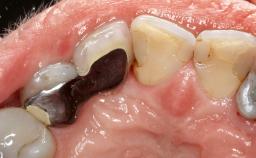

A 37-year-old male patient was referred to the Department of Periodontology at the University of Bern, Switzerland, by a private dentist. Tooth 21 had been lost due to trauma and had been replaced with an implant and a cemented single crown. The tapered-effect tissue-level implant had a diameter of 4.1 mm, a length of 12 mm, and a sandblasted and acid-etched (SLA) surface (Straumann Dental lmplant System; Institut Straumann AG, Basel, Switzerland). The metal-ceramic crown had been cemented permanently, leaving a submucosal gap between the implant shoulder and the crown margin. Absence of marginal bone loss apical to the polished transmucosal neck of the implant could be observed .